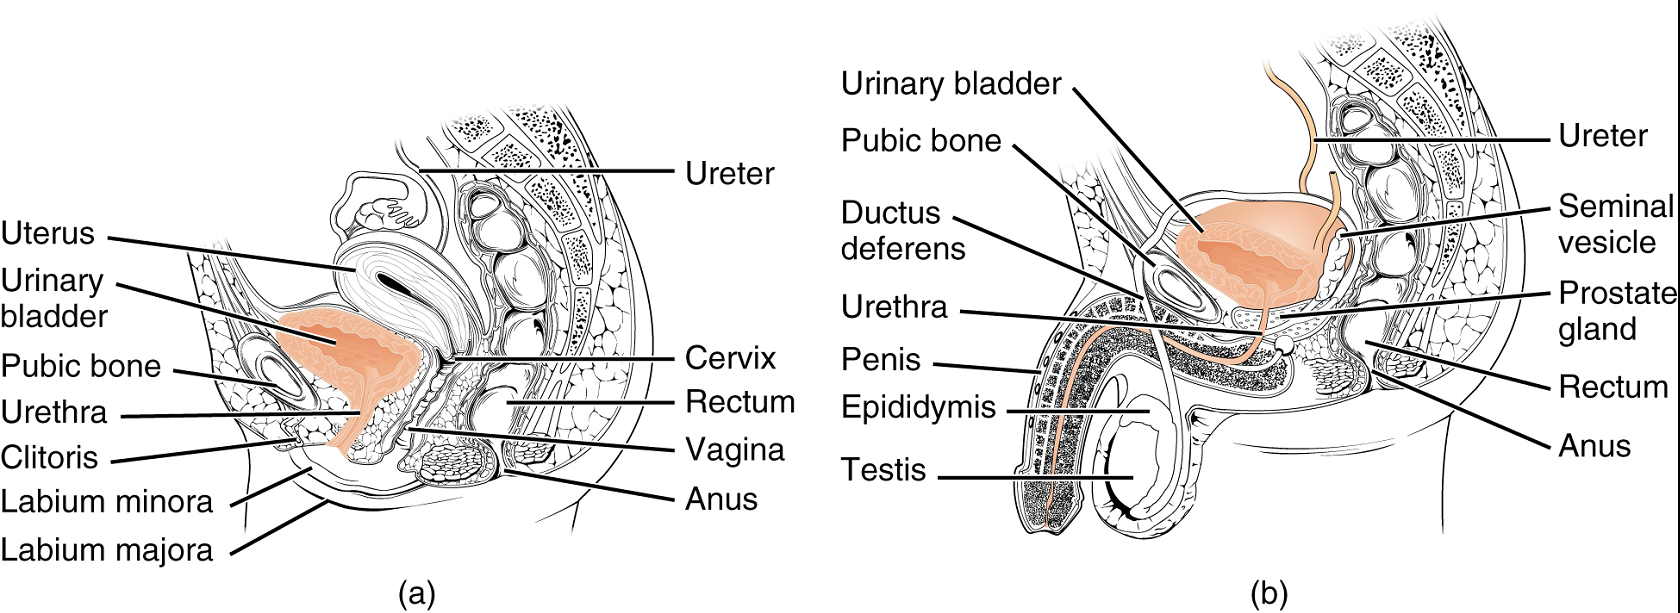

Bladder

The urinary bladder collects urine from both ureters (Figure 5). The bladder lies anterior to the uterus in females, posterior to the pubic bone and anterior to the rectum. In males, the anatomy is similar, minus the uterus, and with the addition of the prostate inferior to the bladder. The bladder is partially retroperitoneal (outside the peritoneal cavity).

Urethra

The urethra transports urine from the bladder to the outside of the body for disposal. The urethra shows significant anatomic difference between males and females; all other urine transport structures are identical (Figure 6).

Female Urethra: Its short length, about 4 cm, is less of a barrier to fecal bacteria than the longer male urethra and the best explanation for the greater incidence of urinary tract infections in women.

Male Urethra: The male urethra passes through the prostate gland immediately inferior to the bladder before passing below the pubic symphysis (Figure 6b). The urethra passes through the deep muscles of the perineum and exits at the tip (external urethral orifice) of the penis. Mucous glands are found along much of the length of the urethra and protect the urethra from extremes of urine pH. Male urethra also serves as the duct through which semen (fluid containing sperms) is discharged.